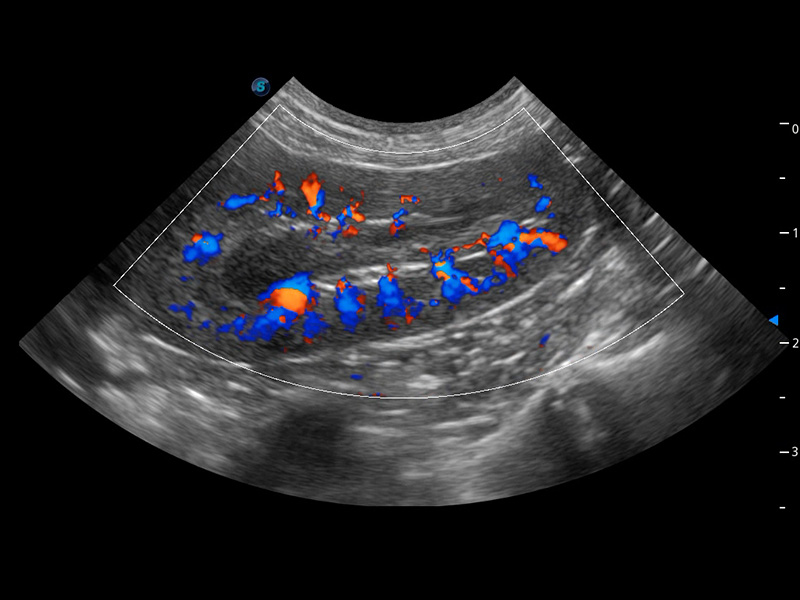

ProPet 60 作为一款高端台式动物超声设备,为动物医生的日常诊断提供了一系列贴合动物临床需求、解决临床实际问题的高级成像功能。凭借全系列高清探头,满足医生对腹部、心脏、生殖、浅表、肌骨等成像的所有需求,切实帮助您提升检查效率,提高诊断信心。

动物是人类最亲密的朋友和最值得信赖的伙伴。乐玩lewin国际也一直致力于探索动物专用的超声影像解决方案。 全新推出的ProPet系列,是乐玩lewin国际在动物超声影像智能化、专业化、精准化的一次跨越式革新。动物不能用言语来表述自己的不适,通过超声影像,ProPet系列搭建了动物医生与不同物种沟通的“桥梁”,为动物医生注入了“治愈之力”。